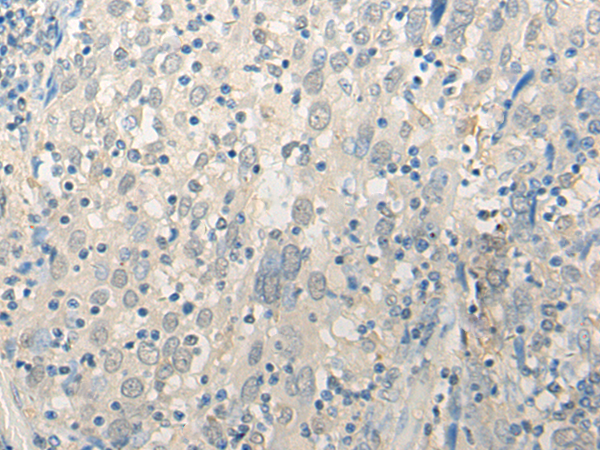

IHC positive control: |

Human cervical cancer |

IHC Recommend dilution: |

20-100 |